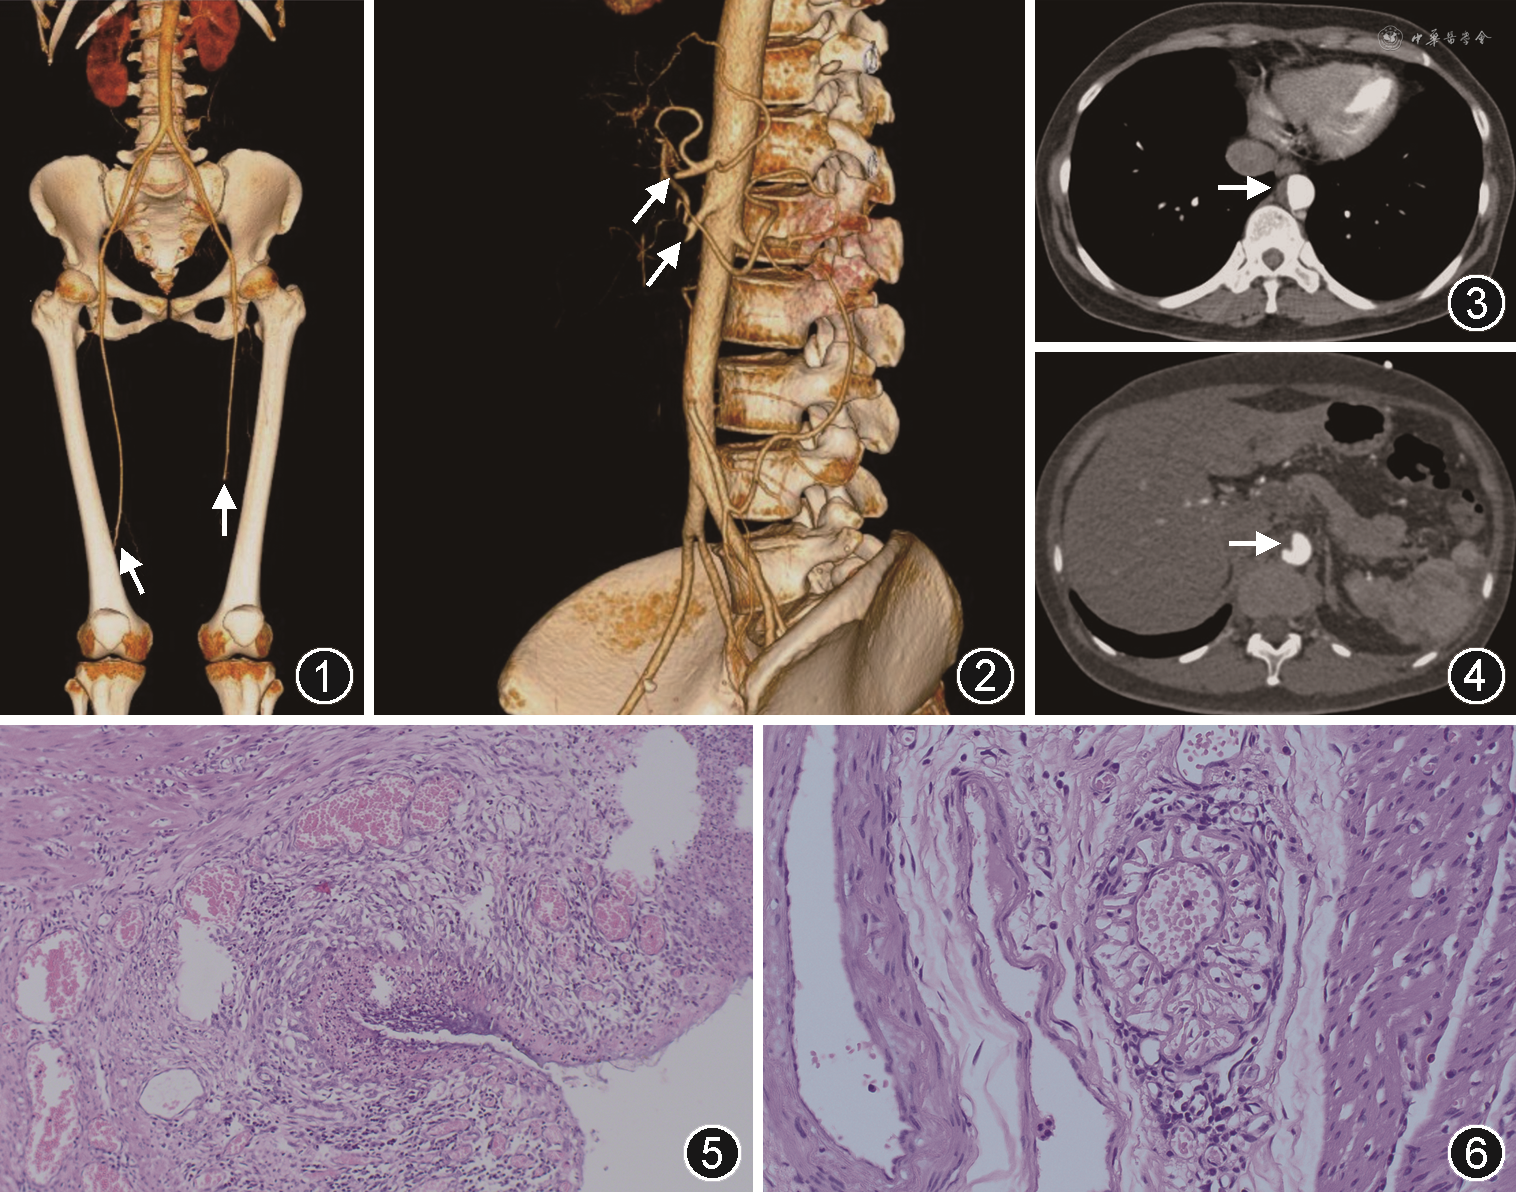

患者女,45岁,主因“间歇性跛行3个月余、腹胀2个月”于2019年6月20日就诊于北京协和医院风湿免疫科。患者3个月前无诱因突发双侧下肢间歇性跛行,行走200 m困难,伴趾端苍白,无关节红肿、疼痛及活动受限,无静息痛,无下肢溃疡、麻木,未诊治。2个月前出现上腹胀痛,排气排便减少,无反复恶心、呕吐,于当地医院急诊诊断为“肠梗阻”,胃肠镜检查无明显异常,对症治疗6 d后好转。外院查抗β2-糖蛋白1(β2-GPI)抗体阳性,下肢动脉造影提示:双下肢腘动脉血栓性闭塞。双侧髂动脉、颈动脉、椎动脉、锁骨下动脉、腹主动脉、腹腔干、肠系膜上动脉未见明显异常。胸部CT示双侧少量胸腔积液。超声心动图、肝胆胰脾超声、正电子发射计算机断层扫描(PET/CT)躯干断层显像未见明显异常,为进一步诊治收入北京协和医院风湿免疫科。入院时患者空腹及餐后腹胀、恶心,偶有呕吐,仍存在下肢间歇性跛行,无发热、口腔或外阴溃疡,无雷诺现象,无皮疹、瘀点瘀斑、黑便、齿龈出血等其他特殊症状。婚育史:孕5产1,第3胎为孕12周时自然流产,原因不详,未行病理检查。既往史、个人史、家族史无殊。体格检查:体温36.6 ℃,血压117/77 mmHg(1 mmHg=0.133 kPa),心率83 次/min,呼吸23 次/min,一般状况可,双侧腘动脉以下血压未测得,膝关节以下皮温减低,双足背动脉未触及。贫血貌,双肺呼吸音清,未及干湿啰音。全腹软,上腹鼓音,左季肋区、左腰区轻度深压痛、反跳痛,肠鸣音活跃。血常规:白细胞9.79×109/L,血红蛋白81 g/L,平均红细胞体积69.4 fl,平均红细胞血红蛋白量20.5 pg,血小板 598×109/L;粪便潜血(+);尿常规:阴性。肝肾功能:白蛋白26 g/L,肌酐57 μmol/L。凝血:凝血酶原时间13.1 s,纤维蛋白原5.12 g/L,D-二聚体2.06 mg/L FEU;易栓症相关检查[蛋白C、蛋白S、活化蛋白C(APC)抵抗]:阴性。超敏C反应蛋白(hsCRP)16.12 mg/L,红细胞沉降率(ESR)56 mm/1h,IgA 4.69 g/L,补体C3 1.512 g/L。抗核抗体谱、抗可溶性核抗原(ENA)抗体谱、抗磷脂抗体谱、系统性血管炎相关抗体谱阴性,狼疮抗凝物(LA)1.17,Coombs试验阴性。血清M蛋白及肿瘤标志物无异常。骨髓涂片:缺铁性贫血,余阴性。CT血管造影(CTA)、血管超声:胸主动脉及腹主动脉附壁血栓形成,腹腔干、肝总动脉、脾动脉、肠系膜上动脉多发闭塞,伴侧支循环形成,右肾缺血性改变,门静脉血栓形成;左侧股深动脉血栓形成、双侧腘动脉闭塞(图1~4)。

入院后考虑患者主动脉、多发腹腔及下肢动脉血栓明确,炎症指标增高,需警惕系统性血管炎,在予以依诺肝素钠6 000 U每日2次,阿司匹林100 mg每日1次治疗同时,加用甲泼尼龙40 mg每日1次静脉注射,治疗5 d后患者食欲、进食量及步行距离较前改善,左腹深压痛、反跳痛消失,便隐血转阴,夜间偶有恶心,无腹胀、呕吐、腹泻、黑便,入院11~13 d未排便,排气可,考虑患者平素每2~3日排便1次,未予特殊处理。入院14 d患者中午饱餐后突发左腹部针扎样疼痛,疼痛数字评分法(NRS)7~8分,排气消失,肠鸣音减低,3 h后疼痛加重,部位扩展至脐区和右下腹,拒按,并逐渐出现神志淡漠,四肢皮温下降,血压105/56 mmHg,心率97次/min,呼吸25次/min,血氧饱和度97%,体温正常。急行腹盆增强CT示第3组小肠穿孔,于当晚行急诊剖腹探查手术。术中见腹腔内大量黄色浑浊腹水,距屈氏韧带约35 cm处见一纤维条索将空肠粘连于侧腹壁,近端空肠明显梗阻、扩张,伴肠壁增厚,远端对系膜缘侧肠壁见一穿孔,直径约2 cm。术中切除穿孔处及周边粘连小肠约10 cm,行小肠端端吻合。术后病理回报:小肠黏膜急、慢性炎症,部分缺血性坏死,伴溃疡及穿孔,溃疡周围肉芽组织增生,浆膜面可见炎性渗出物附着(图5、6)。术后患者恢复良好,无腹痛腹胀、恶心呕吐。根据患者的临床特点考虑诊断白塞病(BD),继续甲泼尼龙40 mg每日1次联合环磷酰胺0.4 g每周1次静脉输注治疗,并先后恢复肝素及阿司匹林,复查腹盆增强CT未见新发栓塞、出血,或残留感染灶。出院后继续环磷酰胺0.4 g每周1次静脉输注,泼尼松改为60 mg每日1次口服,4周后每周减5 mg,减至30 mg每日1次后每周减2.5 mg,最终10 mg每日1次维持,同时联合华法林4.5 mg每日1次抗凝,监测国际标准化比值在2.0~3.0,阿司匹林100 mg每日1次抗血小板。术后12个月随诊期间,患者病情稳定,无任何不适。复查炎症指标正常,抗磷脂抗体及LA均为阴性。